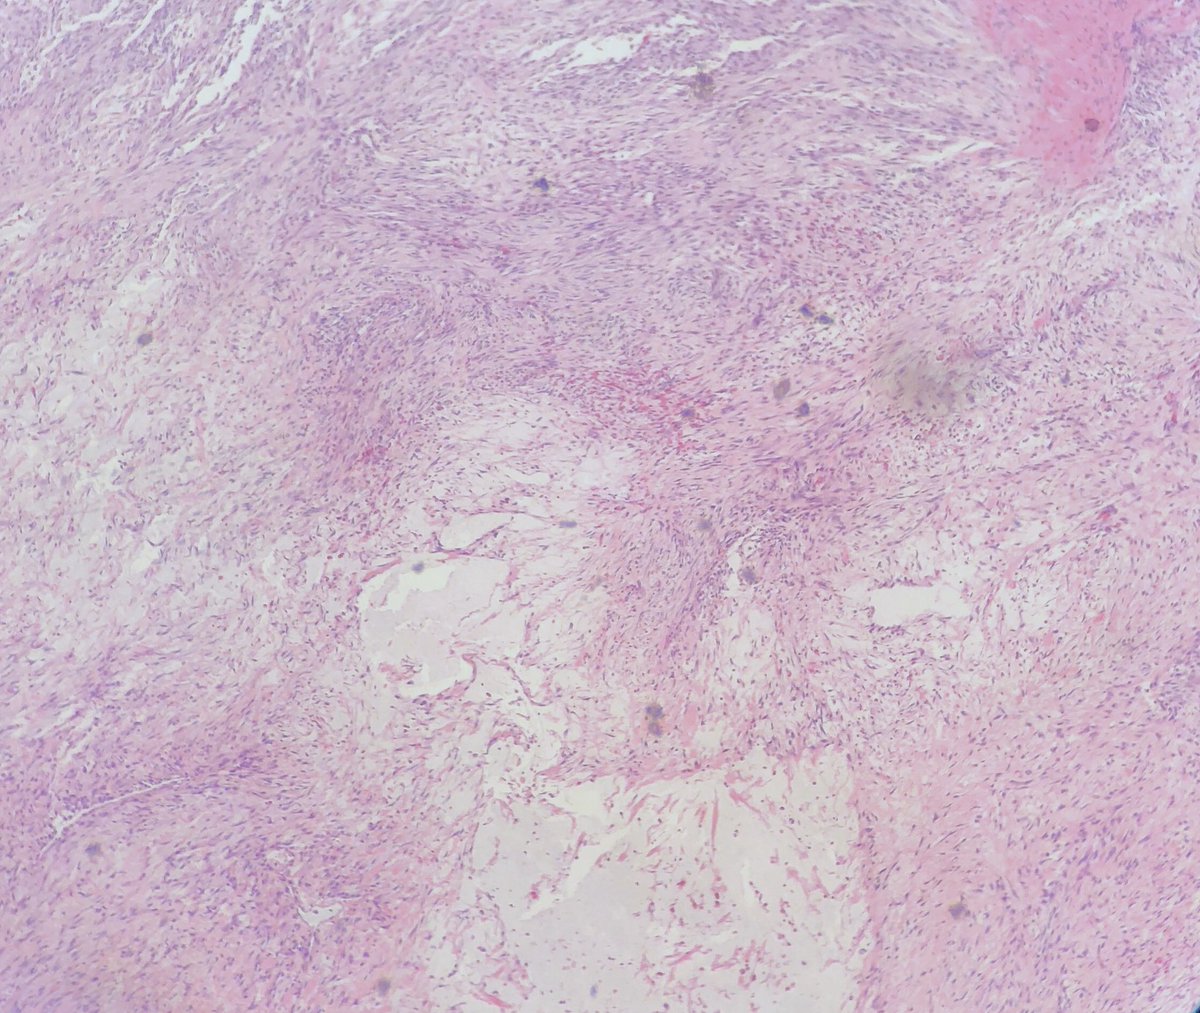

Nice nodular fasciitis

#pathtweetorial. Sometimes they arise on head/neck (esp in kids). For more examples of nodular fasciitis, check out my video (one of 1st YouTube videos I made...quite different from my current style!) https://youtu.be/2jAjK8C7Y6c#pathology#BSTpath#dermpathhttps://twitter.com/JScapaPathMD/status/1213497816988803072 …

A beautiful

45 year old man with a postauricular mass

spindled and stellate plump cells in fascicular arrangement with myxoid stroma and extravasated RBCs

SMA+, Keratin-, S100-, cytoplasmic b-Catenin

USP6 gene rearranged